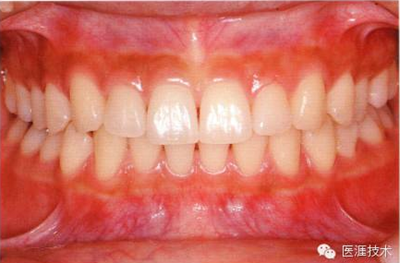

健康牙周組織的牙齦邊緣呈珊瑚粉,邊緣牙齦略呈圓弧狀。牙間可見三角形的牙間乳頭,牙齦邊緣相連呈貝殼形。

附著齦與游離齦相連時,有時有游離齦溝存在(成人的30~40%)。

附著齦通過膠原纖維牢固結(jié)合骨骼與牙骨質(zhì),因此可見不可動、硬而緊繃的點彩(橘皮樣點狀凹凸)。

從牙齦牙槽粘膜到根尖有牙槽粘膜。牙槽粘膜為暗紅色,與骨骼結(jié)合較松,故可動。